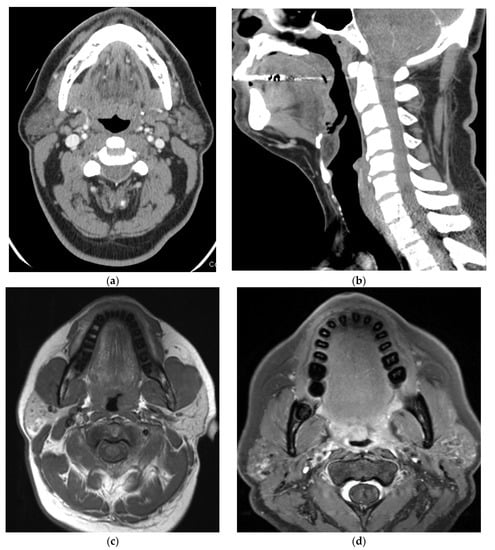

5. Imaging of Oropharyngeal Cancers

8.1. Initial Staging